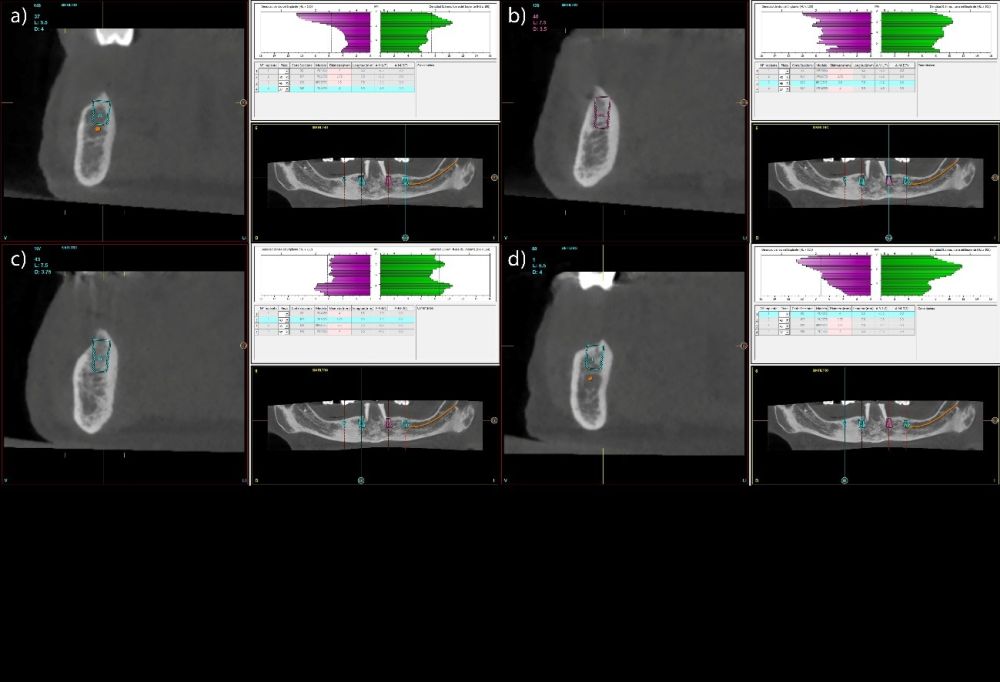

Se llevó a cabo un estudio retrospectivo sobre una cohorte consecutiva de pacientes rehabilitados mediante prótesis híbridas mandibulares soportadas por cuatro implantes. Los tratamientos fueron realizados en un centro privado especializado en implantología oral (Vitoria, España) durante los años 2001-2018. Solo se incluyeron en el análisis aquellos pacientes que hubieran completado de forma íntegra el seguimiento clínico y radiográfico hasta la fecha actual, lo que garantizó la disponibilidad de registros comparables a lo largo de todo el periodo de observación. Todos los pacientes presentaban mandíbulas completamente edéntulas rehabilitadas mediante cuatro implantes, existiendo dos grupos: 4 implantes largos interforaminales sin angulación y 4 implantes cortos distribuidos en la mandíbula totalmente edéntula de forma biomecánicamente favorable. La intervención quirúrgica fue llevada a cabo por el mismo profesional siguiendo el protocolo de fresado biológico46, que se caracteriza por trabajar a bajas revoluciones y sin irrigación externa, favoreciendo la preservación del hueso autólogo y optimizando la estabilidad primaria del implante. Durante la inserción se registró el torque final alcanzado y se documentaron las características anatómicas del lecho mediante el Cone-Beam Computed Tomography (CBCT) preoperatorio, a partir del cual se obtuvieron los valores de densidad ósea expresados en unidades Hounsfield (HU). Los implantes se clasificaron posteriormente en dos grupos según su longitud: cortos (<10 mm) y largos (≥10 mm).

Todas las rehabilitaciones protésicas siguieron un mismo protocolo estandarizado. Una vez completada la cirugía, se procedió a la carga inmediata mediante una prótesis provisional atornillada sobre pilares transepiteliales, diseñada para distribuir las cargas de forma progresiva durante los primeros meses. Pasado un intervalo de entre seis y doce meses, y tras confirmar la estabilidad clínica y radiográfica de los implantes, se elaboró la prótesis definitiva. Esta consistió en una estructura metálica, revestida con resina acrílica, conformando una prótesis híbrida atornillada que mantenía el mismo esquema funcional que la provisional. El control radiográfico se llevó a cabo mediante radiografías panorámicas estandarizadas, realizadas siempre con el mismo sistema de posicionamiento reproducible, que incluía referencias en el suelo para los pies y apoyos simultáneos en glabela y mentón, con el fin de mantener constantes las relaciones angulares y minimizar la distorsión entre visitas. La medición de la pérdida ósea marginal se efectuó sobre la última radiografía panorámica obtenida bajo este protocolo de estandarización. Una vez digitalizada la imagen, se procedió a su calibración mediante un software específico (Digora for Windows, SOREDEX Digital Imaging Systems), utilizando como referencia una longitud conocida (el propio implante). Tras incorporar dicho valor, el programa corregía la magnificación inherente de la técnica panorámica, permitiendo realizar mediciones lineales exactas y exentas de distorsión. La pérdida ósea marginal se cuantificó en las superficies mesial y distal de cada implante, expresándose siempre como valor absoluto.

Fueron evaluadas 26 prótesis híbridas mandibulares soportadas por cuatro implantes, lo que genera un total de 104 implantes. De estas 26 prótesis, 12 fueron prótesis sobre implantes cortos (longitud < 10 mm) y 14 como prótesis sobre implantes largos (≥ 10 mm). La muestra presentó un claro predominio femenino, con 21 mujeres (80,8%) y 5 varones (19,2%). La edad media de los pacientes fue de 69,7 ± 11,2 años en el momento del inicio del estudio. A nivel de implante, la densidad media del hueso receptor fue de 866.16 ± 146.35 HU, mientras que el torque medio de inserción alcanzó 47.88 ± 9.01 Ncm. En cuanto a los diámetros de los implantes, en el grupo de los implantes cortos, el más frecuente fue el de 3,5 mm con un 56,5% de los casos, mientras que en el grupo de los implantes largos el diámetro predominante fue para 3,5 y 3,75 mm con un 32,1% para cada una de las categorías (Figura 1.a). En cuanto a la distribución de las longitudes, en el grupo de los implantes cortos, la más frecuente fue 7,5 mm con un 54,3% mientras que en los implantes largos la más frecuente fue 10 mm (47,2%) (Figura 1.b).